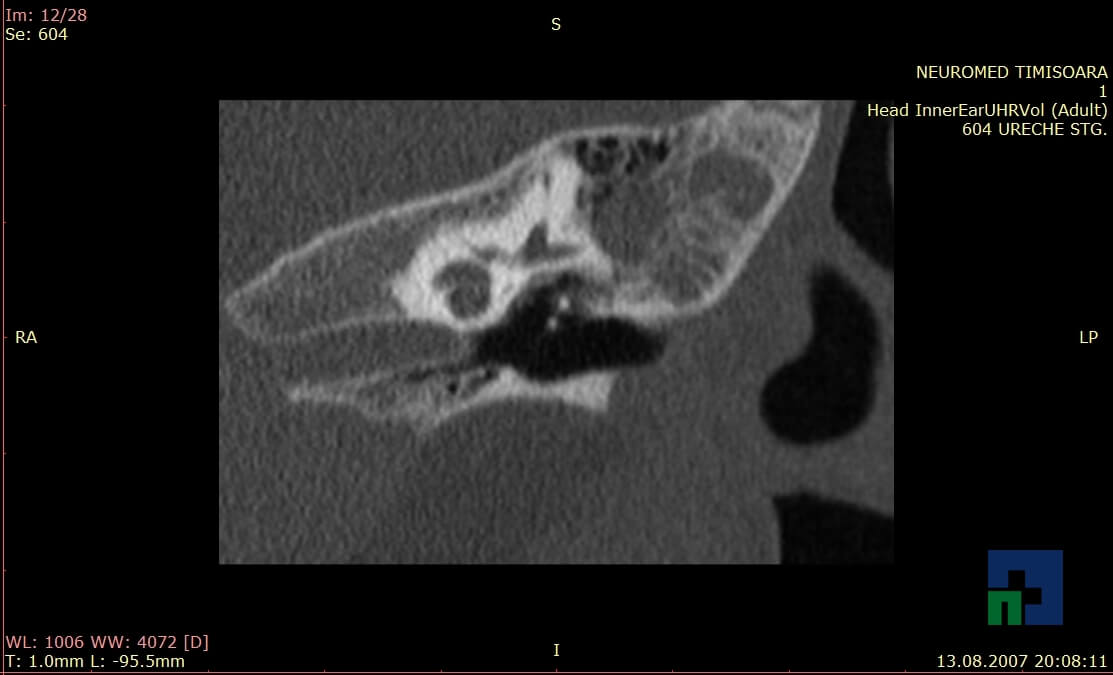

- Diagnosticul traumatismelor de bază de craniu

- Diagnosticul fistulei LCR